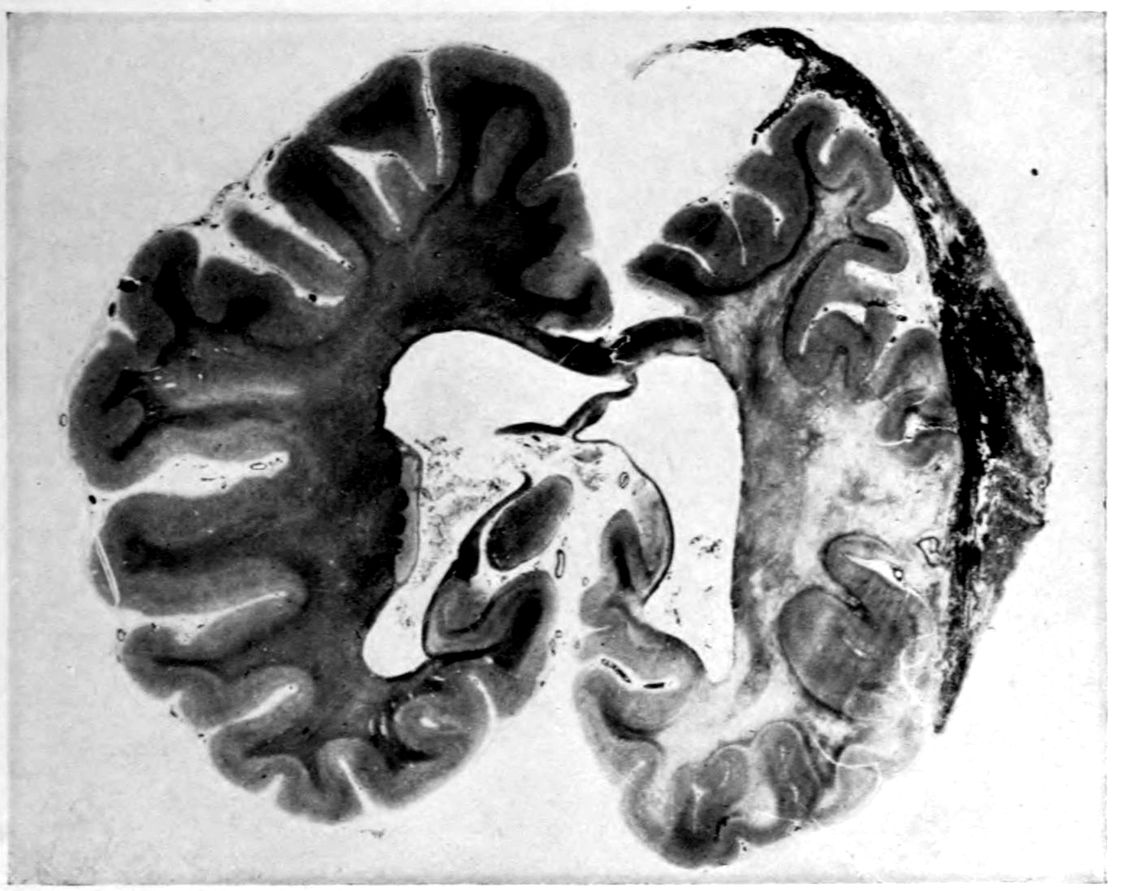

Case 4. James Pierce was an almshouse transfer to the Danvers Hospital in his fiftieth year. He died three years later. The accompanying brain pictures demonstrate so extensive a lesion of the left hemisphere that it is of great interest to determine if possible the genesis and course of his disease. It appears that syphilis had been acquired somewhere about the age of 38 or 40, so that the total duration of the process was between 13 and 15 years. In Pierce’s forty-third or forty-fourth year, he had a shock while walking in the streets of his native city, whereupon he was subsequently transferred to the Danvers Hospital, whose data have been summed up as follows (we are obliged to Dr. Charles T. Ryder for these data):

The autopsy findings were as follows:

Head: Calvarium of moderate thickness; diploë present; dura slightly adherent over bregmatic region. Longitudinal sinus contains cruor clot. Dura is somewhat thickened and slightly more opaque than normal. Pacchionian granulations, small but fairly numerous. Pia contains throughout a considerable excess of clear 44serous fluid. The convolutions in general are of good breadth and proportion. There is an atrophic area roughly circular in outline and about 2 cm. in diameter in the posterior part of the right third frontal convolution corresponding to Broca’s area on the opposite hemisphere. The space thus formed is filled with edema held by the pia. On the left side is a similar subpial collection which covers the site of the posterior portions of all of the third frontal convolutions, parts of the lower end of the precentral convolution, and the whole of the first temporal convolution, which have disappeared entirely. The basal vessels show slight changes.

Cerebellum and basal ganglia are grossly normal.

The spinal membranes are negative. The regions of the pyramidal tracts in the cord are firm, project slightly from surface of section, and are china white.

Summary: Here is a picture made up almost purely of Vascular Neurosyphilis, with Secondary Spinal (Pyramidal Tract) Changes. Doubtless the genesis of this picture is allied to that of Case 1 (Alice Morton) and to that of the terminal vascular complications in a tabetic, Case 2 (Francis Garfield).

Vascular neurosyphilis—effects of syphilitic thrombosis of Sylvian artery 10 years before death. (Case 4.)

Case 4. (See previous figure for brain lesion.) Three levels of the spinal cord showing unilateral pyramidal tract sclerosis, 10 years after cerebral thrombosis.